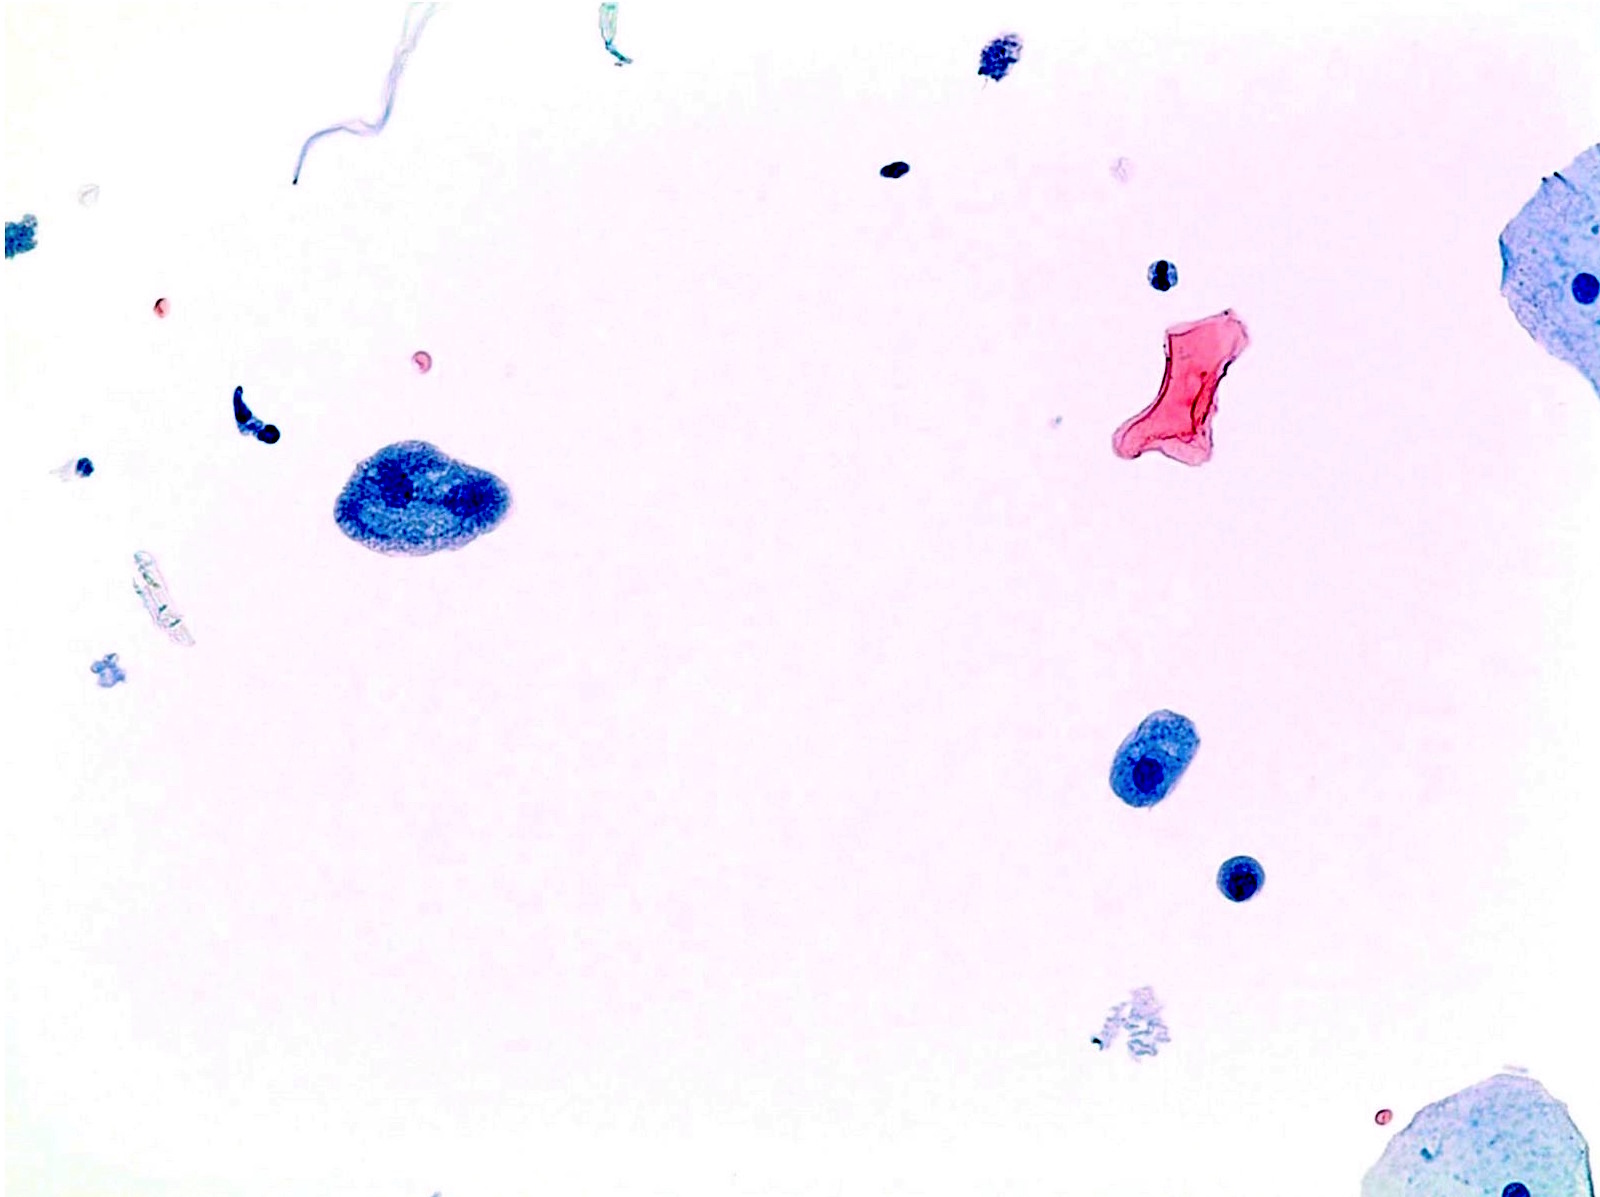

Negative for High Grade Urothelial Carcinoma (NHGUC)

- To minimize lumping everything into the "atypical" category, the terminology Negative for High Grade Urothelial Carcinoma includes all entities that pose no significant risk to the patient for developing HGUC based upon available studies

- This term also clarifies the goal of the Paris System - to highlight those cases at risk for HGUC

- For example, radiation associated atypia is classified as Negative for High Grade Urothelial Carcinoma and not atypical

- A urine sample (voided or instrumented) is considered Negative for High Grade Urothelial Carcinoma if any of the following components are present:

- Benign urothelial, squamous and glandular cells

- Benign urothelial tissue fragments

- Changes associated with stones

- Viral cytopathic effect due to polyoma virus

- Post therapy effect, including epithelial cells from urinary diversions